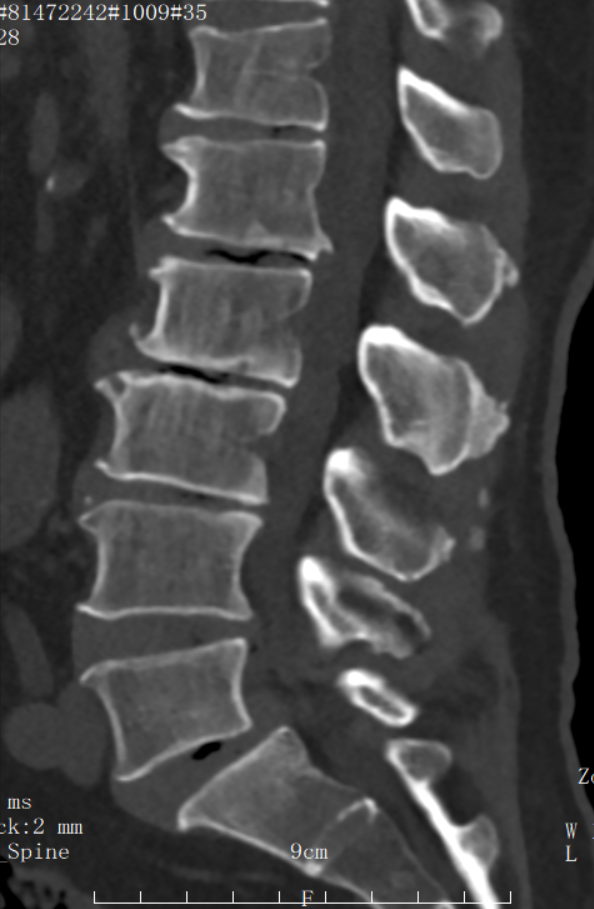

▲術前CT檢查

據悉,患者年逾七旬,因長期腰腿疼痛、麻木困擾,行走困難,生活質量急劇下降。入院后,經詳細檢查,被確診為“腰椎滑脫伴椎間盤突出”。這是一種常見的脊柱退行性疾病,對于高齡患者而言,傳統的開放手術創傷大、出血多、恢復慢,手術風險相對較高,讓許多老人望而卻步。